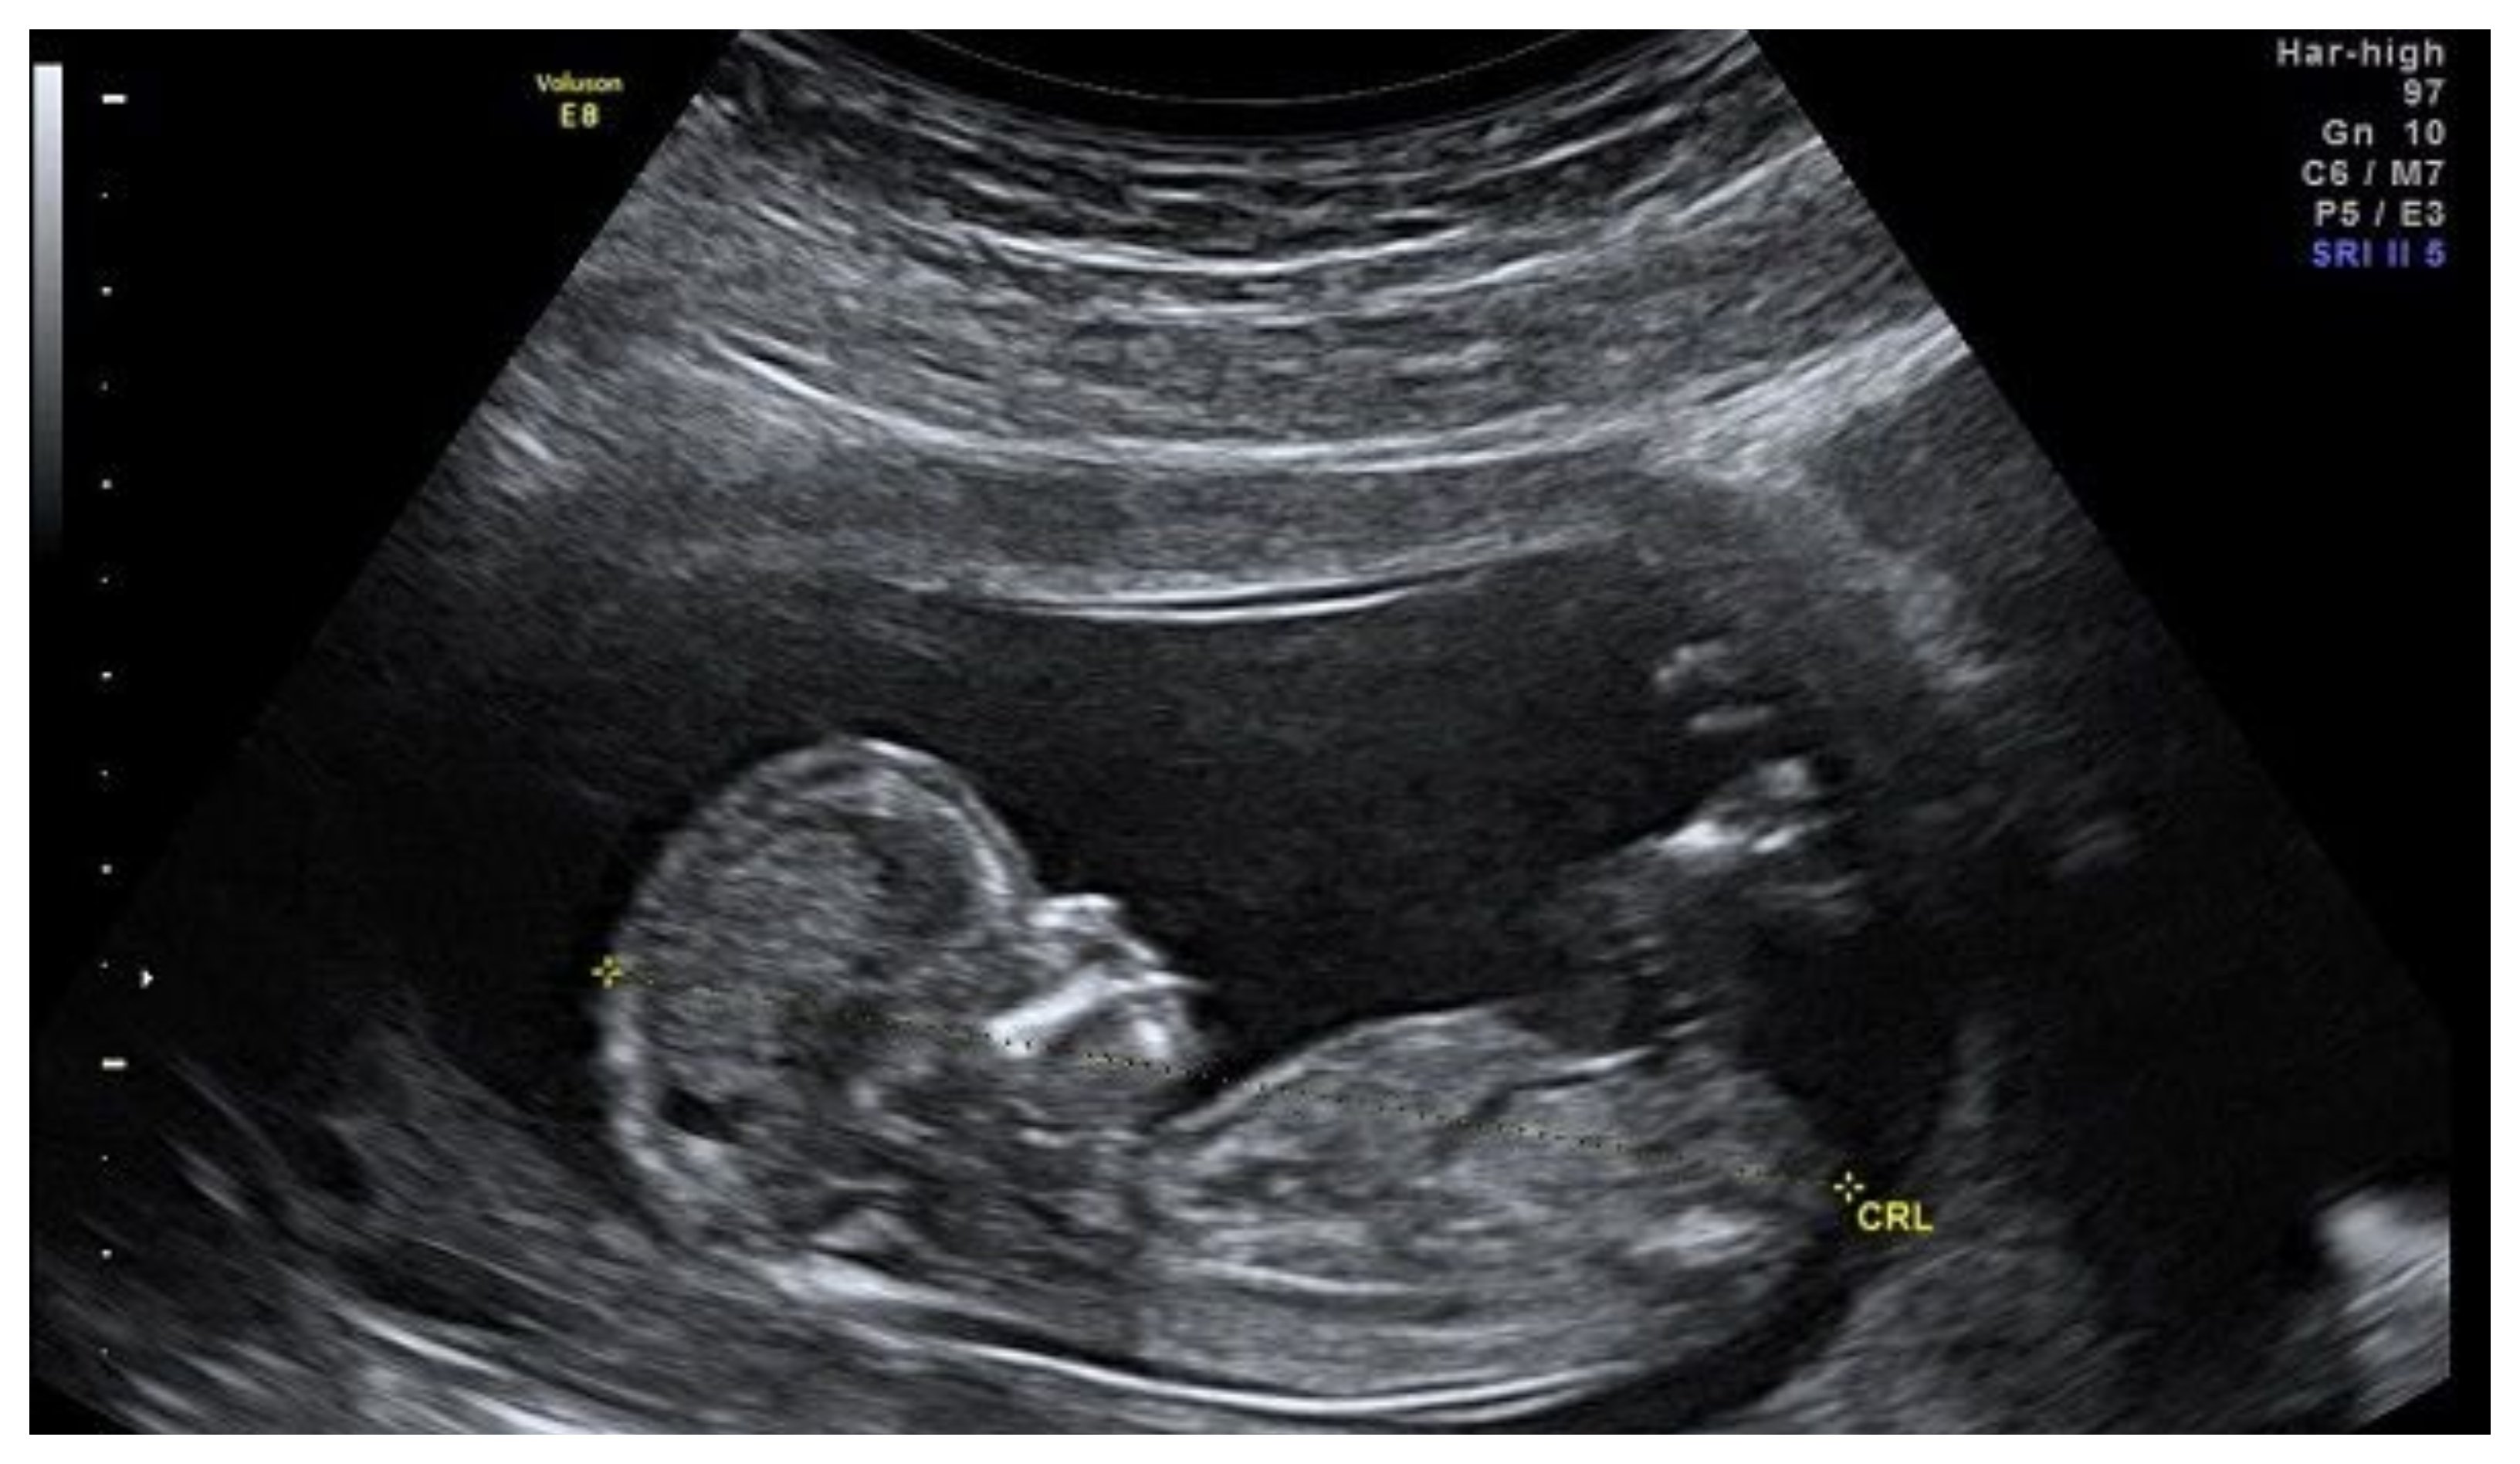

En marzo de 2020, cuando comenzó la pandemia de Covid-19, el Departamento de Salud anunció que permitiría a las mujeres realizar abortos con medicamentos en casa durante las primeras 10 semanas de embarazo. Las reglas temporales les permitía acceder a los fármacos sin visitar primero una clínica, sino que solo bastaba una consulta telefónica o en línea.

Un aborto médico, a veces llamado aborto químico, es un proceso de dos pasos que implica la ingestión de mifepristona y luego misoprostol. El primero mata de hambre al feto al bloquear los efectos de la hormona progesterona, y esto induce a un aborto espontáneo; mientras que el segundo se toma hasta dos días después e induce el parto.